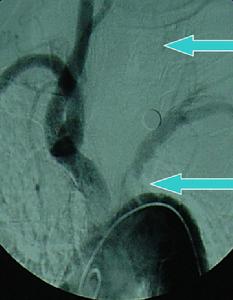

2.數字減影血管造影(DSA)重點觀察主動脈弓兩側鎖骨下動脈及頸總動脈等血管。若發現鎖骨下或頭臂幹上,椎動脈起始部的近心段有嚴重狹窄(多為管腔的85%)或幾乎閉塞,甚至同時可見造影劑經對側椎動脈上行至基底動脈又下行(逆流)至患側鎖骨下動脈的遠心段更可確診。